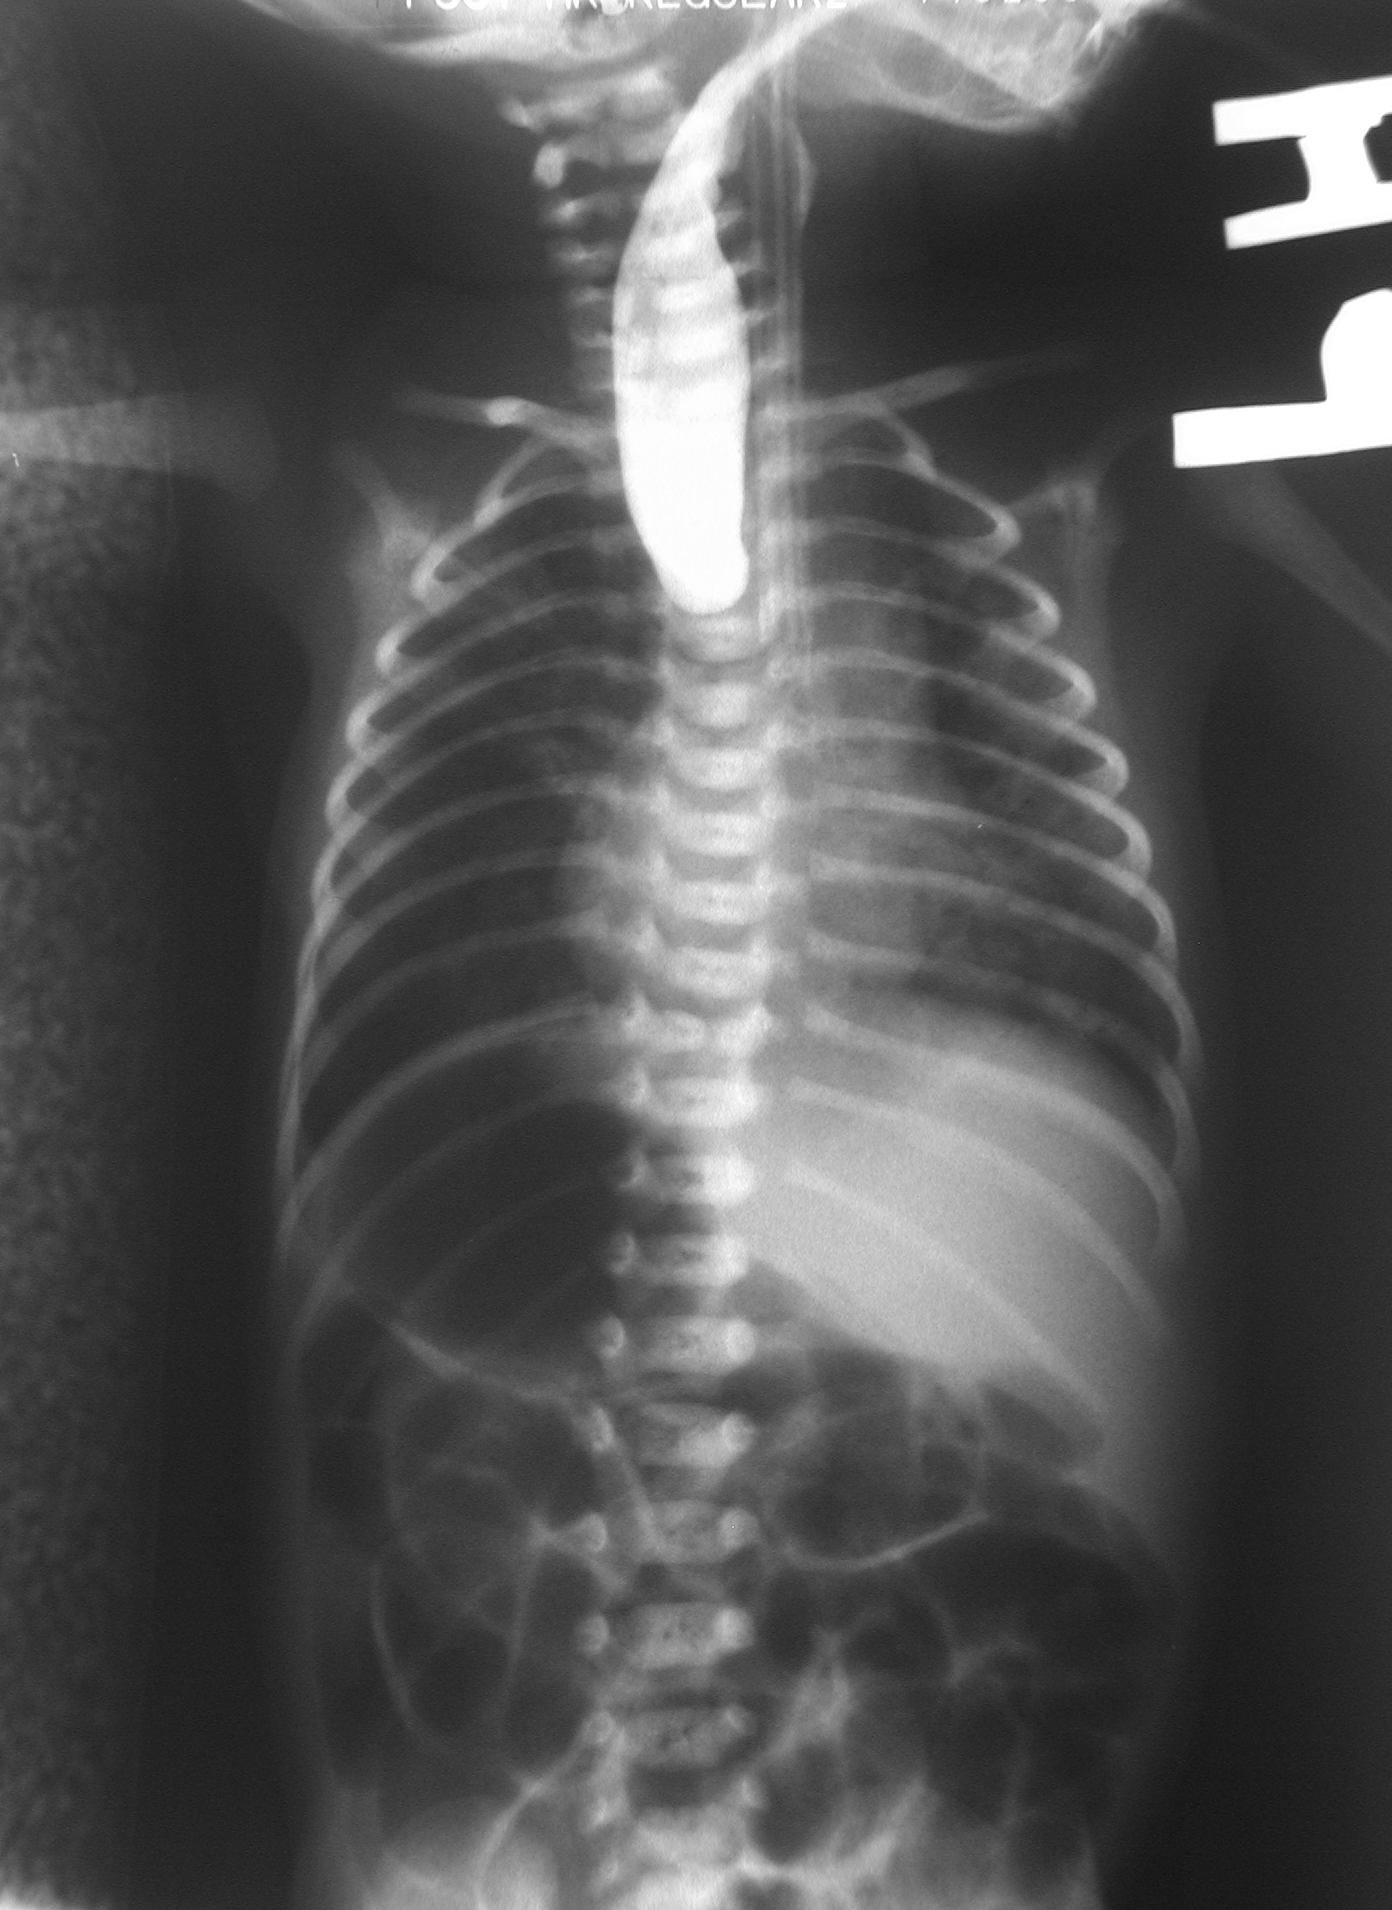

흉부와 복부의 단순 X선 영상. 영양관이 폐쇄된 식도를 지나가지 못하고 있다

폐쇄가 일어난 부분 위쪽의 상부 식도에 조영제가 들어간 것을 보여주는 단순 X선 촬영 영상.

단순 X선 영상에서는 영양관이 식도를 통과하지 못하고, 상부 식도에 꼬인 채로 남아 있게 되는 모습을 발견할 수 있다.[39][11]